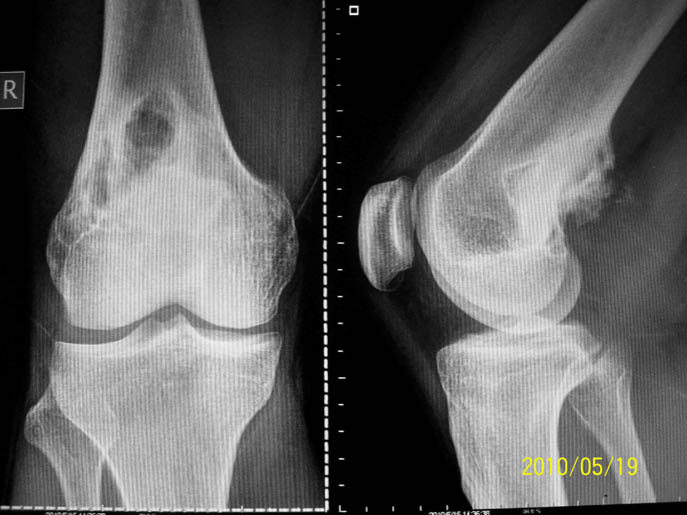

以下是引用zhangzhongshou在2010-5-21 7:33:00的发言:[br]1\\胫骨非骨化性纤维瘤。[br]2、不典型:骨软骨瘤?建议ct/mri进一步检查。

以下是引用随光逐影在2010-5-21 17:25:00的发言:[br]病例1:右胫骨下段非骨化性纤维瘤。[br]病例2:右股骨下段软骨黏液样纤维瘤?非骨化性纤维瘤?